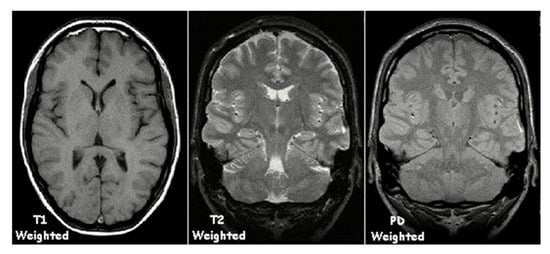

- Grover, V.P.B.; Tognarelli, J.M.; Crossey, M.M.E.; Cox, I.J.; Taylor-Robinson, S.D.; McPhail, M.J.W. Magnetic Resonance Imaging: Principles and Techniques: Lessons for Clinicians. J. Clin. Exp. Hepatol. 2015, 5, 246–255. [Google Scholar] [CrossRef] [Green Version]

- Chavhan, G.B.; Babyn, P.S.; Thomas, B.; Shroff, M.M.; Haacke, E.M. Principles, Techniques, and Applications of T2*-Based MR Imaging and Its Special Applications. Radiographics 2009, 29, 1433–1449. [Google Scholar] [CrossRef] [PubMed] [Green Version]